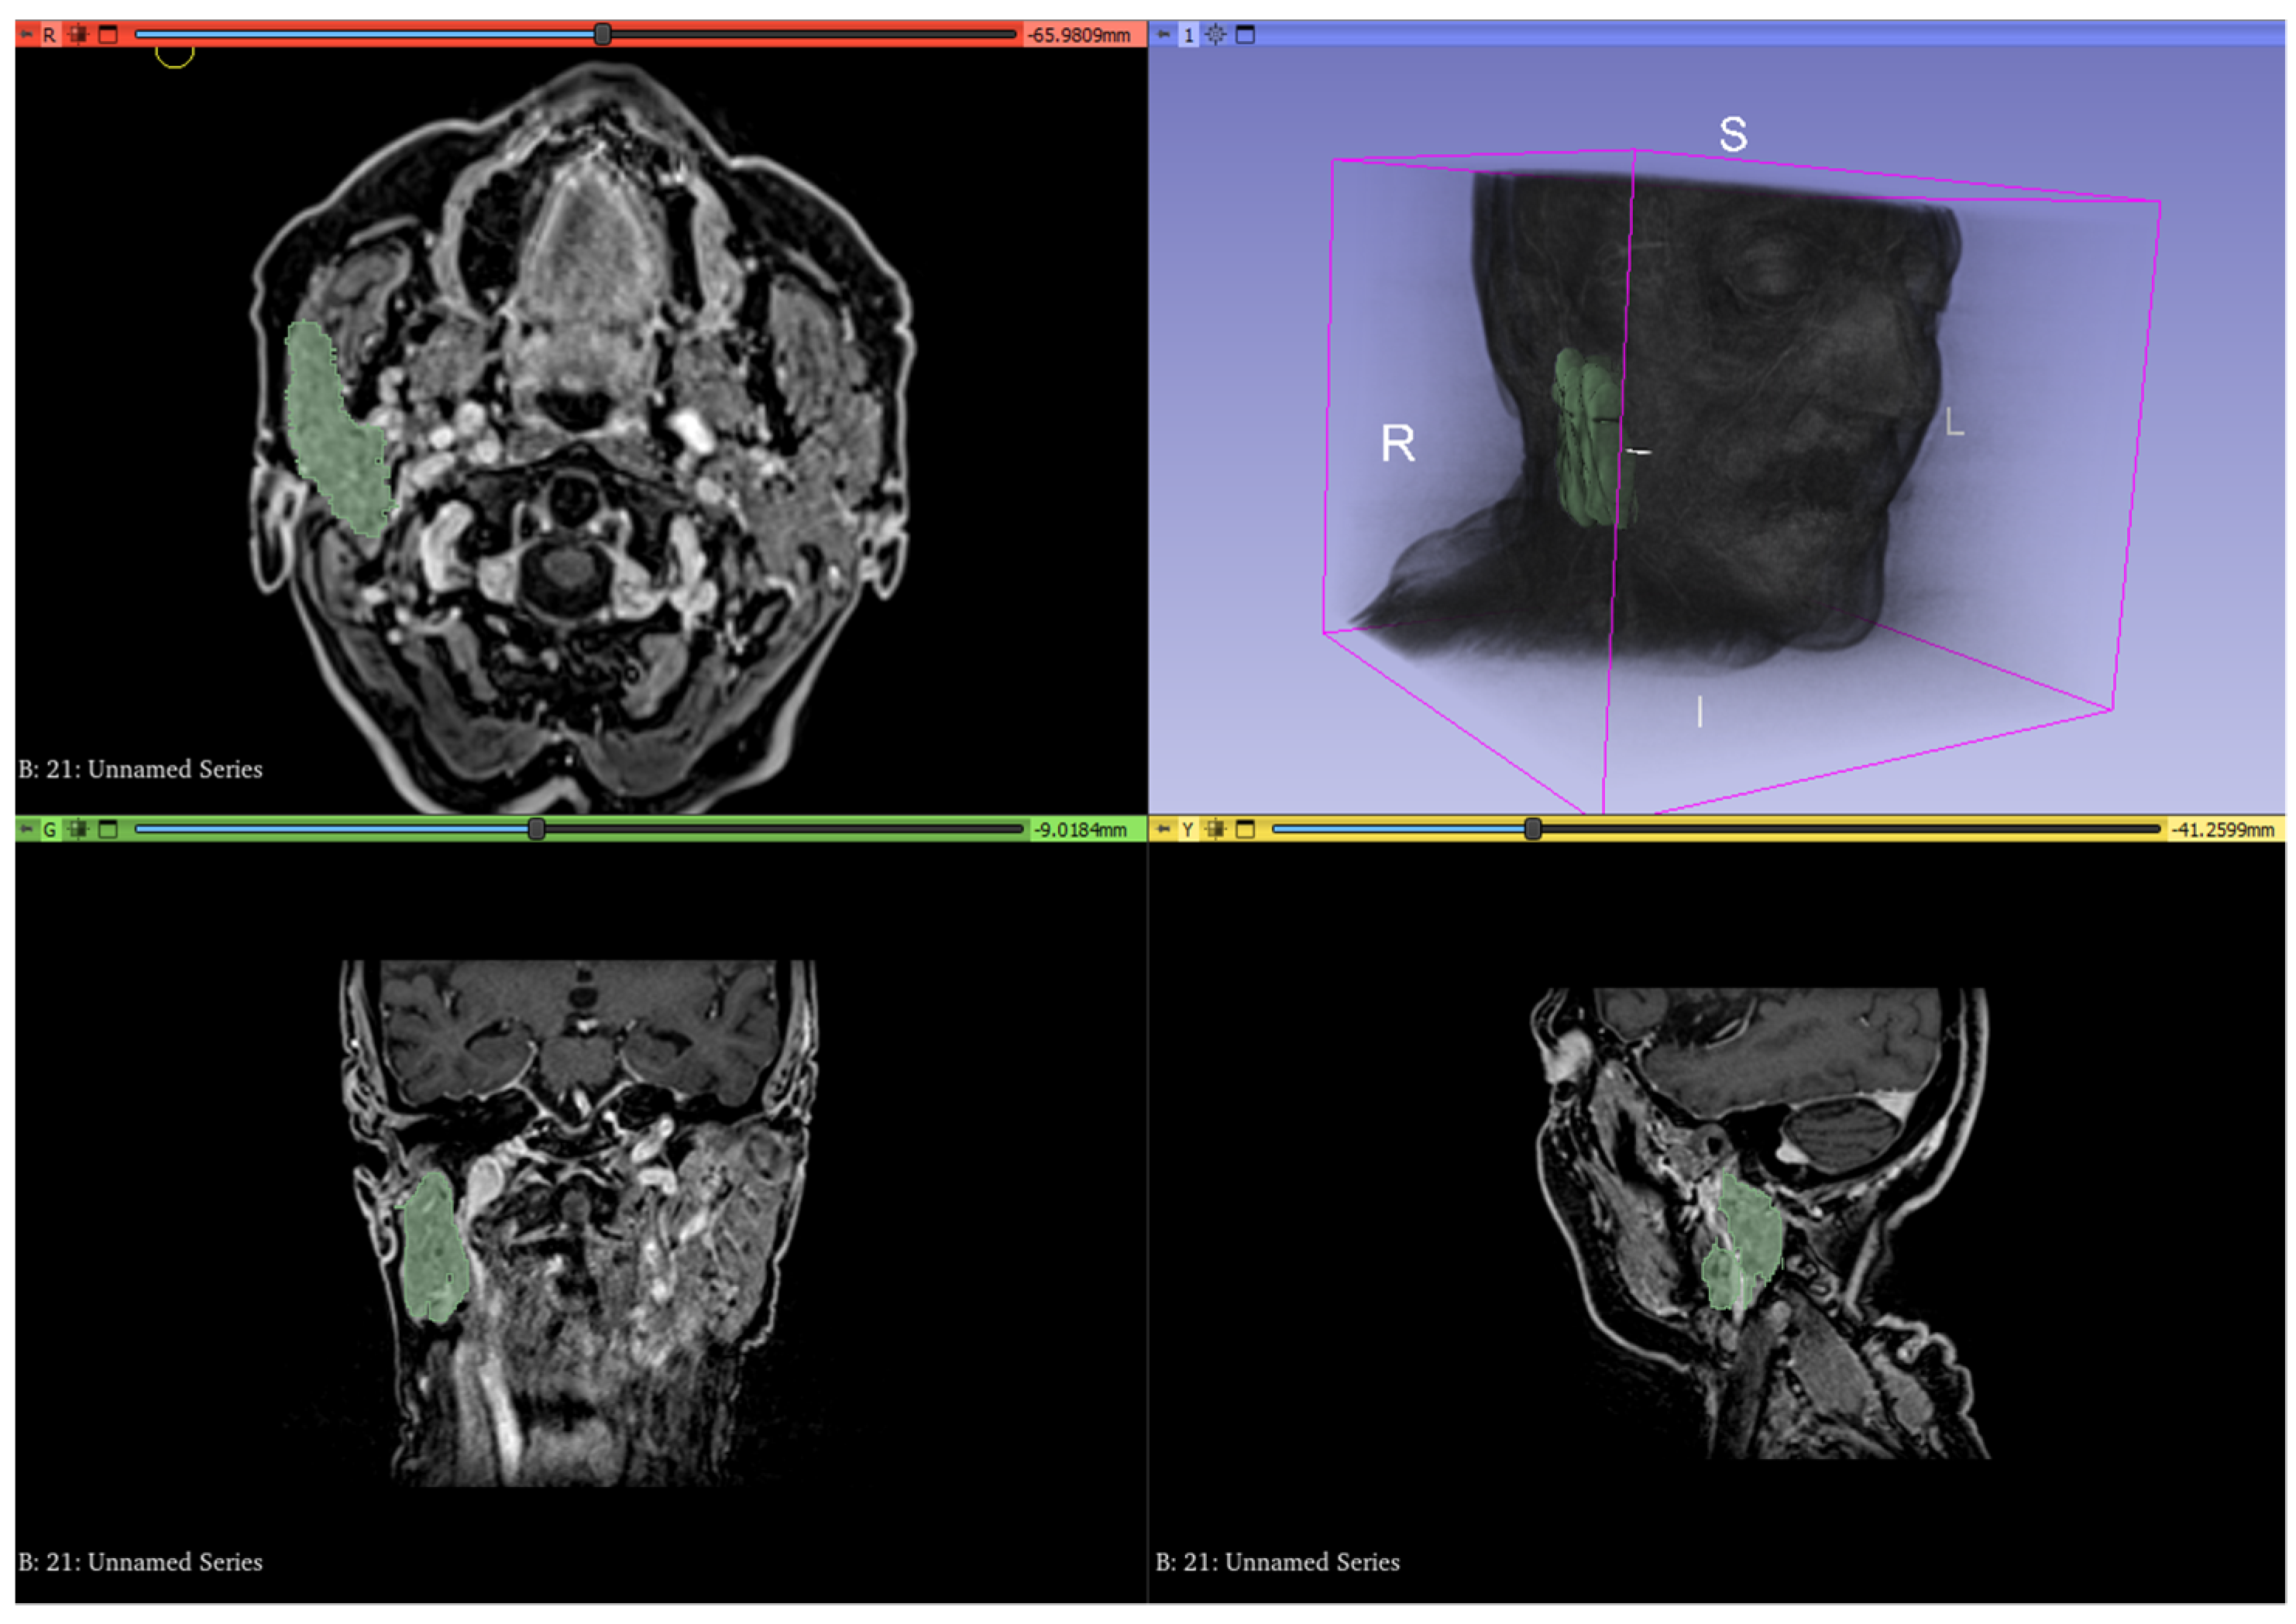

2.4. Texture Analysis

The MRI images obtained with T1 post-contrast sequences and the ADC maps before and after RT were imported into 3D slicer (www.3dslicer.org (accessed on 12 February 2022)) v10.4.2 software. The parotid and submandibular glands located on the same side of the oropharyngeal cancer, corresponding to the irradiated side, were segmented for the entirety of their volumes by a radiologist with 3-years’ experience in head and neck cancer using the “segmentation wizard” extension for 3D slicer (Figure 3). Specifically, the segmentation of the gland located on the irradiated side was performed on CE-T1 sequences both before and after RT. The same method was carried out on the ADC maps thus resulting in a total of 4 different segmented volumes per gland. This process resulted in a total number of 216 volumes being segmented with 4 submandibular and 4 parotid gland volumes investigated for each of the 27 patients. Texture features were analyzed and extracted from such volumes using the extension “Pyradiomics” for 3D slicer.

Figure 3.

Whole volume segmentation of the right parotid gland using 3D slicer software on contrast-enhanced T1 sequences. The entire process was performed for submandibular and parotid glands of the irradiated side on both pre- and post-RT contrast-enhanced T1 sequences and ADC maps.